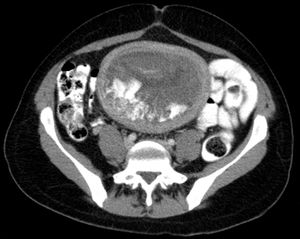

Hydatidiform mole on CT, axial view